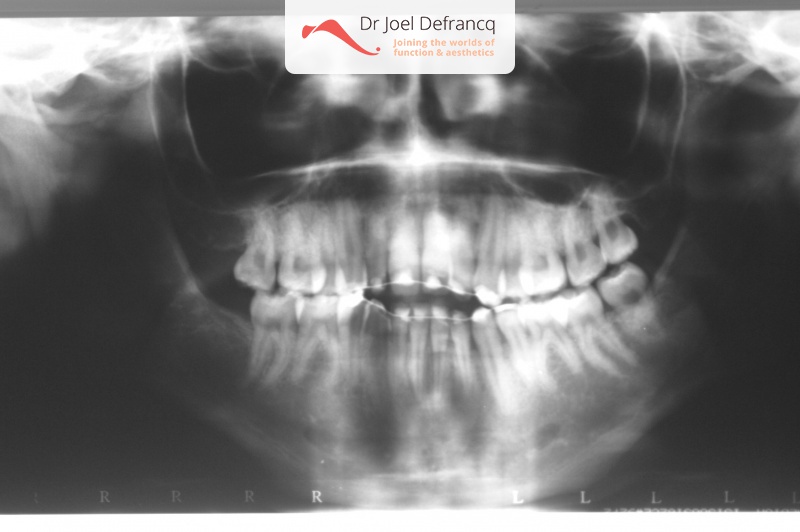

Mick: Open beet, te smalle kaken, tandvleeslach

Diagnose van het gezicht

- Te smalle bovenkaak

- Open beet

Dentale diagnose

- Klasse I